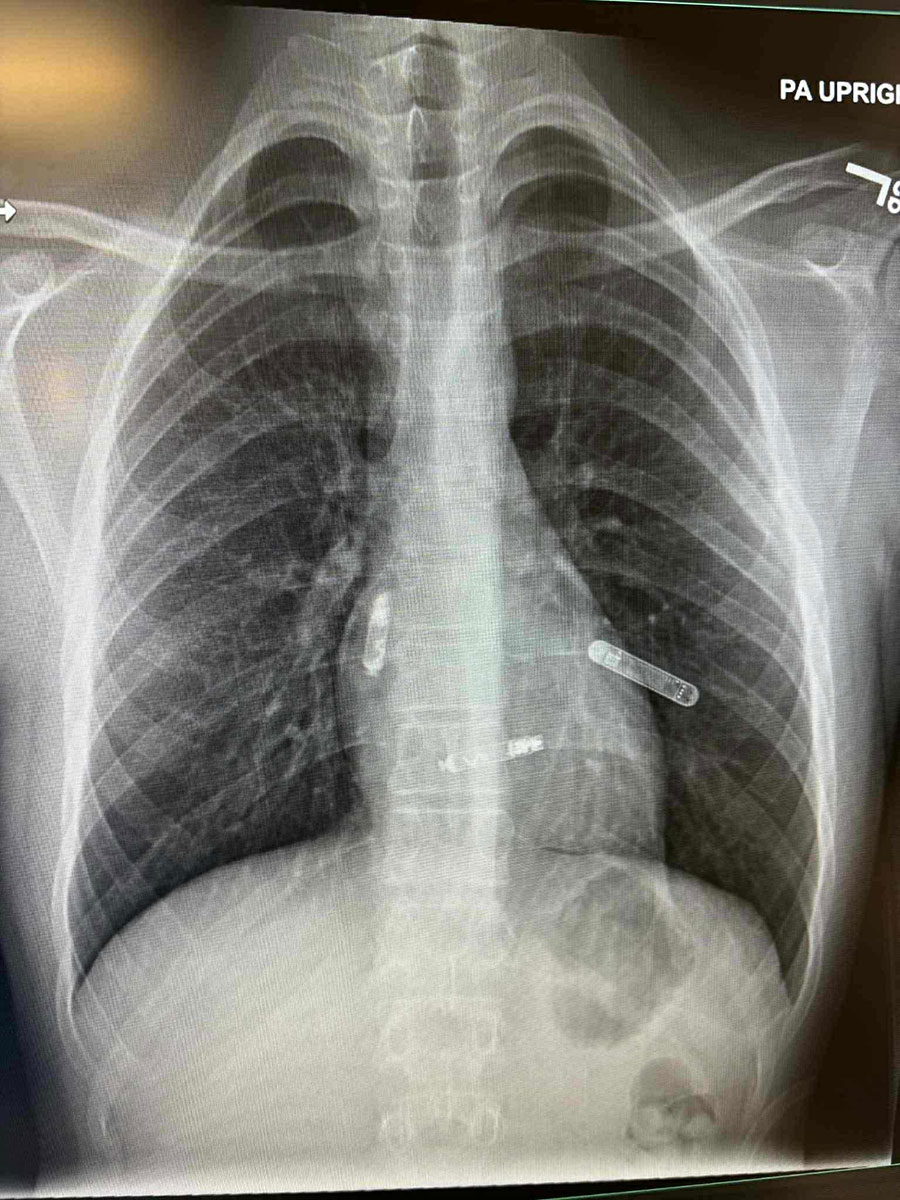

Mostarka dr. Svjetlana Tišma-Dupanović, kardiologinja i pedijatrica, uspješno je pacijentu ugradila dvokomorni pejsmejker izravno u srčane šupljine, u pretklijetku i klijetku, koji sinkronizirano potiču pravilan rad srca.

Tradicionalni pejsmejkeri postavljaju se ispod kože prsnog koša, a žice prolaze kroz vene do srca. Nova tehnologija, koju je primijenila dr. Svjetlana Tišma-Dupanović, omogućuje izravnu ugradnju uređaja unutar srca, bez žica koje prolaze kroz krvne žile.

Ovaj dvokomorni (biventrikularni) pejsmejker sinkronizira rad pretklijetki i klijetki, čime se postiže pravilniji ritam i učinkovitije pumpanje krvi, objavio je dr. Edhem Čustović na svojoj Facebook stranici.